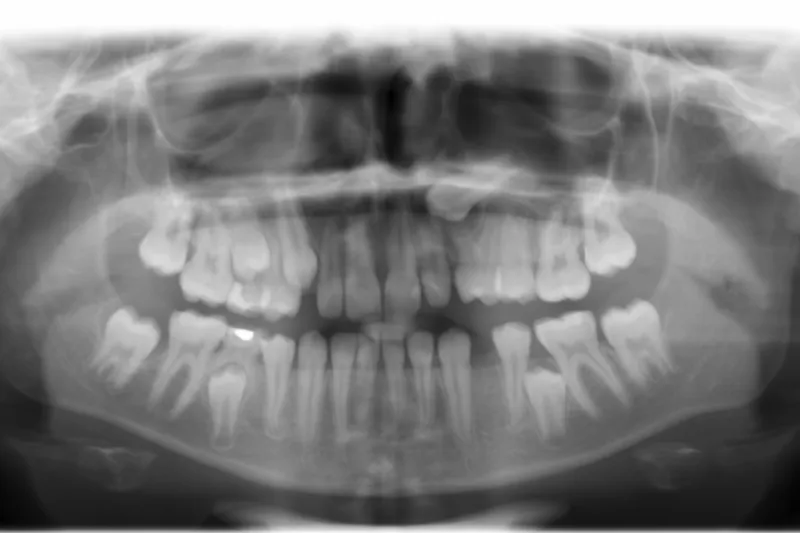

Denne oversigtsartikel redegør for forekomsten af retinerede og ektopisk lejrede hjørnetænder samt belyser de forskellige årsager, der kan føre hertil. I artiklen beskrives også forskellige komplikationer, der kan ses i forbindelse med retinerede og ektopiske hjørnetænder. En af de hyppigste komplikationer er resorption af rødderne på nabotænderne. Det er derfor vigtigt, at de ektopiske hjørnetænder diagnosticeres i tide, så risikoen for komplikationer kan mindskes ved rettidig behandling.

Med undtagelse af tredje molar er permanente hjørnetænder i overkæben de hyppigst forekommende retinerede tænder. Denudering af disse udgør derfor en stor del af de kirurgiske behandlinger foretaget i børne- og ungdomstandplejen.Det er vigtigt, at de diagnosticeres tidligt, så komplikationer som fx rodresorption af nabotænder undgås. Det anbefales, at der allerede fra niårsalderen palperes efter retinerede hjørnetænder i overkæben, og er man i tvivl, bør man supplere den kliniske undersøgelse med røntgenoptagelser. Diagnosticeres retinerede eller ektopiske hjørnetænder tidligt, kan interceptiv behandling iværksættes, fx i form af ekstraktion af de primære hjørnetænder. Opdages de først senere, er der ofte behov for både kirurgisk og ortodontisk behandling.